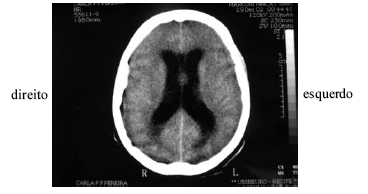

Uma professora de 21 anos de idade apresentou crise convulsiva na fazenda onde dava aulas e, por falta de transporte, somente após quatro horas foi levada ao hospital geral. Ao chegar ao hospital apresentava a seguinte pontuação na escala de coma de glasgow: resposta visual — 3/4, verbal — 3/5 e motora — 4/6. A família revelou que a paciente estava cada vez mais sonolenta e negou sintomas, tais como febre, cefaléia, náuseas, vômitos ou crises epilépticas prévios ao quadro. Foi realizada tomografia de crânio, cujo resultado é mostrado na figura acima, mas não havia neurologista no hospital naquele momento.